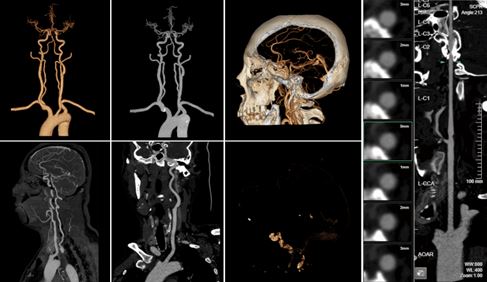

產品名稱:頭頸動脈瘤CT血管造影圖像輔助檢測軟件

申請人:上海聯影智能醫療科技有限公司

聯影智能頭頸血管CT 造影影像輔助診斷軟件全景展示血管

頭頸血管 CT 造影影像輔助診斷軟件,是國內首款基于深度學習技術實現顱內出血分診提示以及測量分析的人工智能醫療軟件。該產品創新性地使用人工智能算法對患者圖像即時進行計算和分析,提高診斷速度,可快速篩選出超急性期和急性期疑似顱內出血患者。